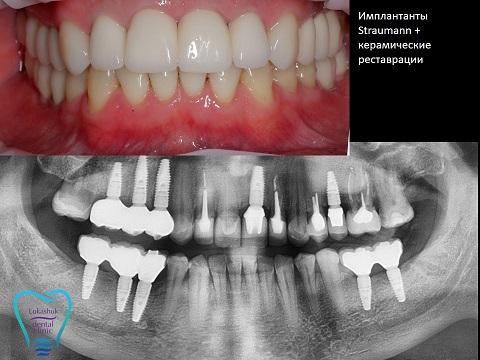

Качественные зубные импланты полностью восстанавливают все функции утраченного зуба и дарят пациенту сияющую улыбку на долгие годы. При отсутствии одного или всех элементов зубного ряда можно получить «новые зубы», которые визуально будут такими, как настоящие, и прослужат долгие годы. Возрастные ограничения для проведения процедуры отсутствуют.

Существует несколько методик имплантации и множество видов зубных имплантов. Важно правильно выбрать тип штифтов, коронок, технологию их установки, чтобы получить отличный результат.

Киевская Клиника стоматологии Лукашука имеет 15-летний опыт работы. Если вам нужен зубной имплант, можете всегда сюда обратиться за помощью.

Правильный выбор клиники и систем имплантов гарантирует отличный результат операции и полное восстановление функций и эстетики зубов.